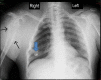

Figure 3. Chest X-ray (Posteroanterior view)

Osteochondromas are seen involving right-sided rib (blue arrow) and right humerus (black arrows).